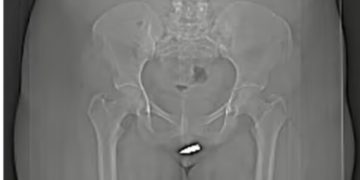

CT scans showed that the bullet had penetrated the clitoris after being fired into her vulva, meaning she needed surgery to have it safely removed.

Doctors said the case is the first of its kind. They can remove the object from the vagina but extra care should be taken not to damage the urethra and pelvic area.